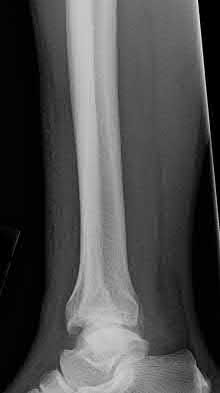

Figure A shows a patient after an open reduction and internal fixation of a bimalleolar ankle fracture.

Egol et al showed that by nine weeks, the total braking time of patients who had undergone fixation of a displaced right ankle fracture returns to the normal, baseline value.

Egol et al, also found that appropriate braking time returns at a point 6 weeks after initiation of weightbearing after treatment of lower extremity long bone and periarticular fractures, as examined with a driving simulator. No differences were seen in return of braking time between periarticular fractures and long bone injuries.